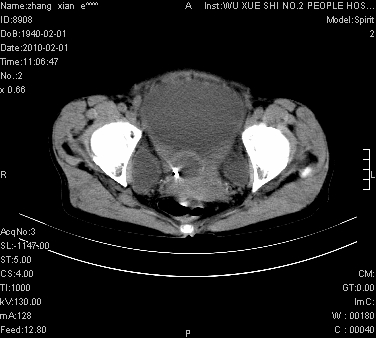

标题: CT24434:70岁 女 腹胀,腹水原因待查 [打印本页]

大量腹水,脾脏囊性占位,子宫颈占位,右侧腹股沟淋巴结肿大,建议+c,先查妇科。

腹盆腔大量积液,子宫增大,子宫颈增大外形不规则,内见低密度影,膀胱后壁显示不清,右腹股沟肿大淋巴结,脾脏囊性占位,子宫颈占位,子宫颈癌?建议增强。

子宫、宫颈占位?转移性腹水?肝性腹水?脾脏囊性占位,囊肿?血管瘤?淋巴瘤?